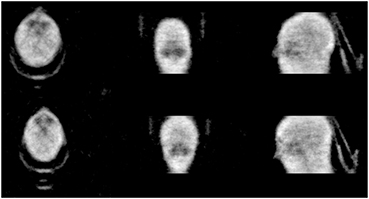

3.3. Reconstructions of cold human volunteers

A study of human subjects was performed in order to observe how well the method performs for the complex structure of the human body. The scan duration times were set to 10 min to simulate fairly realistic scan times and minimize movement from the volunteers. Each volunteer was placed on the bed and inserted into the PET field of view with no activity in or around the PET scanner. A corresponding blank was acquired for 36 h and used for reconstructions of the attenuation maps. The reconstruction algorithm parameters used were 10 iterations with 24 subsets with some regularization for all human volunteer studies. No corrections were performed to the data that corrects for object originating physical effects to the transmission gamma such as scatter or attenuation.

Figure 6 shows two volunteer scans of the head with a carbon fiber head holder in the field of view. From the figure the sinus are visible and the head holder and outline of the head are well defined. Some high density regions are also visible such as parts of the skull and teeth.

Figure 6. Reconstructed transmission image of volunteer's head with head holder. Acquisition performed for 10 min.

Download figure:

Standard image High-resolution imageFigure 7 are reconstructed images of the torso regions of males with weights of ~70 kg. The study of the torso region was performed with both arms up and arms down in a relaxed position. Arms are usually up in a clinical scan unless it is not practical. The arms down case can suffer from truncation of the CT. Using transmission data from Lu-176, the field of view for the attenuation maps are matched to the PET field of view. From both studies, body outline is resolved and internal details such as lungs and the heart are visible. The two studies also differ as the arms down case had the volunteer laying directly on the carbon fiber bed and the arms up case had the volunteer laying on a foam mat between the body and the bed. The bed is easily seen in both images but only having the whole bed visible when the volunteer is lying on a foam mat that separates the body from the bed. The patient's arms up while lying on the foam mat is the typical clinical procedure for imaging in the torso region.

Figure 7. Reconstructed transmission images of volunteer's torsos. Studies were performed with both cases of arms down (top) and arms up (bottom) with acquisition time of 10 min.

Standard image High-resolution imageFigure 8 shows a larger volunteer of weight of ~ 180 kg that would experience truncation within the CT FOV. This study was performed with arms down and 10 min. The circle illustrates the CT's 50 cm FOV and demonstrates even if this study was performed with arms extended overhead, truncation would still occur to this volunteer. It is observed that the body contour is still resolved and some internal structures are visible such as the lungs and heart, but not as clear as the smaller volunteers' case.

Figure 8. Reconstructed transmission image of large human volunteer. Circle illustrates the CT's FOV.